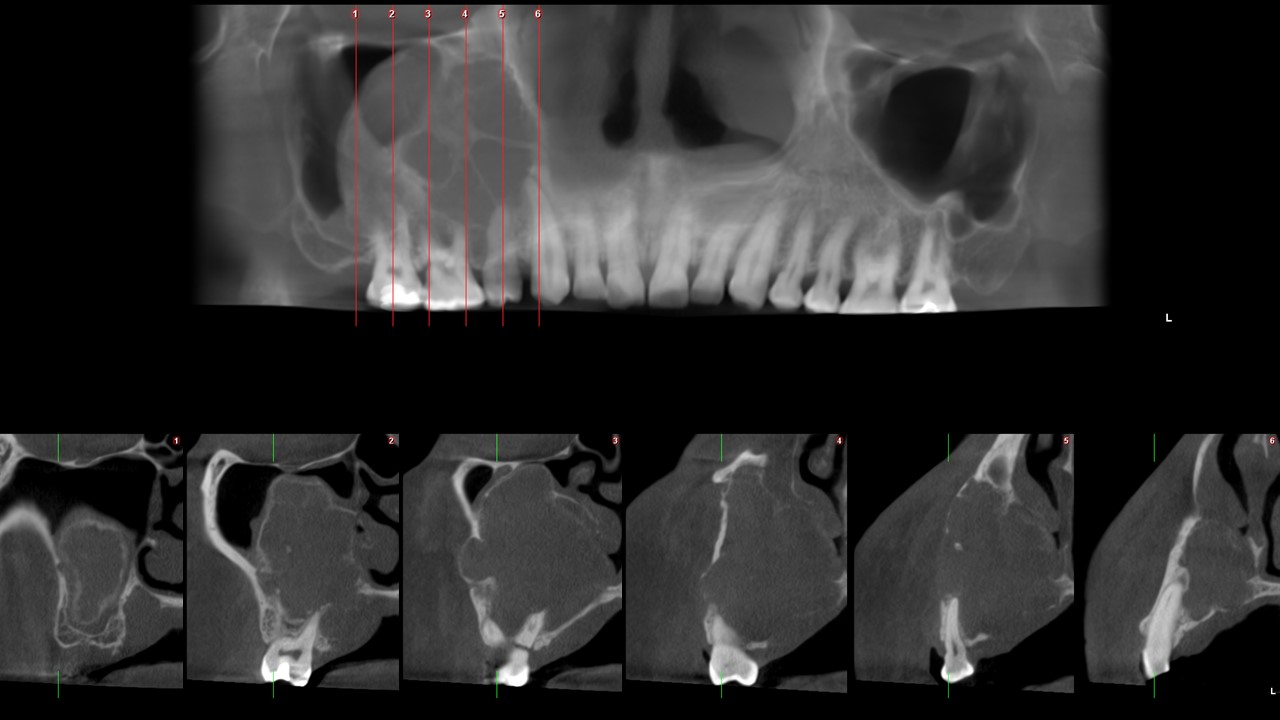

Figura 4

En la vista sagital (Figura 4) confirmamos el ocupamiento del seno maxilar, las corticales de la lesión son delgadas y presenta tenues tabicaciones en su interior. La pieza 16 presenta fractura radicular y la pieza 13 aplanamiento de su contorno apical, lo que sugiere reabsorción radicular externa.